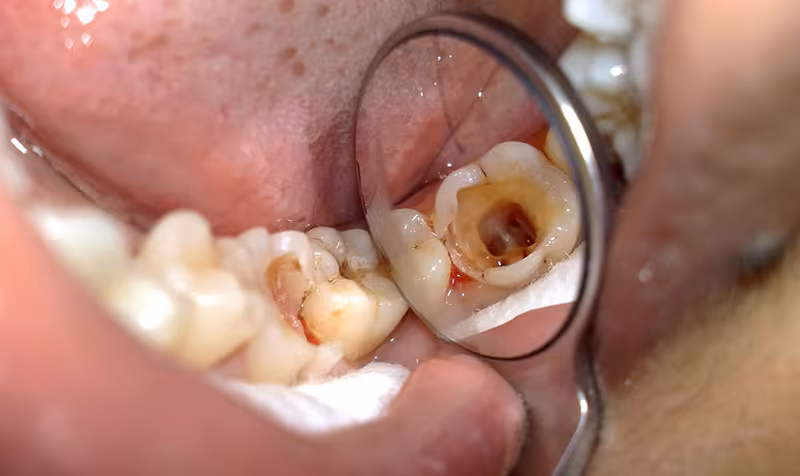

Khi sâu răng ăn vào đến dây thần kinh gây hư tổn tủy răng, nha sĩ sẽ điều trị bằng biện pháp lấy tủy răng để loại bỏ dây thần kinh bị tổn thương. Cách chữa sâu răng bằng việc lấy tủy răng hoàn toàn không gây nguy hiểm đến sức khỏe của bệnh nhân. Hơn nữa đây còn là điều cần thiết để ngăn chặn sự viêm nhiễm lây lan sang các răng khác, gây ảnh hưởng đến chức năng và thẩm mỹ răng.

Giá điều trị tủy răng (lấy tủy răng) thường dao động từ 500.000 – 4.000.000 VNĐ/răng. Chi phí lấy tủy răng sẽ phụ thuộc vào nhiều yếu tố khác nhau như tình trạng viêm tuỷ, công nghệ, cơ sở vật chất,...